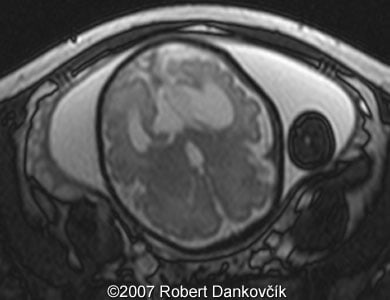

Images 8, 9: MRI; 32 week of pregnancy; transverse sections through the fetal skull showing dilated lateral ventricles and dominant interhemispheric cyst extending to the right.

9

10